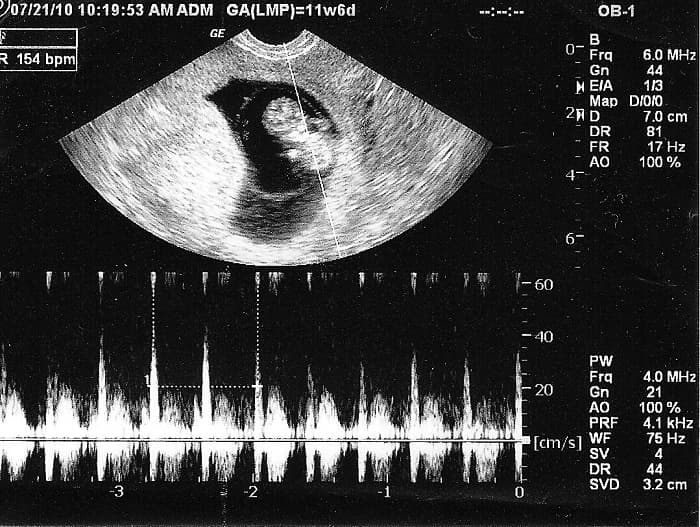

Ngoài thắc mắc mấy tuần có tim thai thì câu hỏi nhịp tim thai thế nào là bình thường, thế nào là bất thường cũng được hầu hết các mẹ bầu quan tâm tìm hiểu. Theo chuyên gia, nhịp đập của tim thai được đánh giá là khỏe mạnh, phát triển bình thường sẽ dao động trong khoảng 120 – 160 nhịp/ phút. Khi bé chuyển động, đạp vào bụng mẹ, nhịp tim có thể lên tới 180 nhịp/phút. Nếu trường hợp tim thai đập vượt quá 180 nhịp/phút, thì cần đưa bà bầu đến ngay các cơ sở y tế để kiểm tra kịp thời vì rất có thể đây là dấu hiệu nguy hiểm của thai nhi. Chính vì vậy siêu âm tim thai là việc rất cần thiết trong thai kỳ, không chỉ ở giai đoạn đầu mà trong suốt quá trình mang thai của bà bầu.

Ở tuần thứ 6 -8 của thai kỳ đã bắt đầu xuất hiện tim thai, vì vậy thời điểm này các mẹ không nên bỏ qua để siêu âm tim thai. Khi ở giai đoạn đầu bắt đầu xuất hiện tim thai, tim của thai nhi tiếp tục phân chia và phát triển, chưa có hình dáng các buồng tim cụ thể. Đến cuối cùng van tim và 4 buồng tim mới hình thành. Chính vì thế, tim thai phát triển tương đối hoàn chỉnh, nhịp tim đập rõ và mạnh vào tuần 20 của thai kỳ.